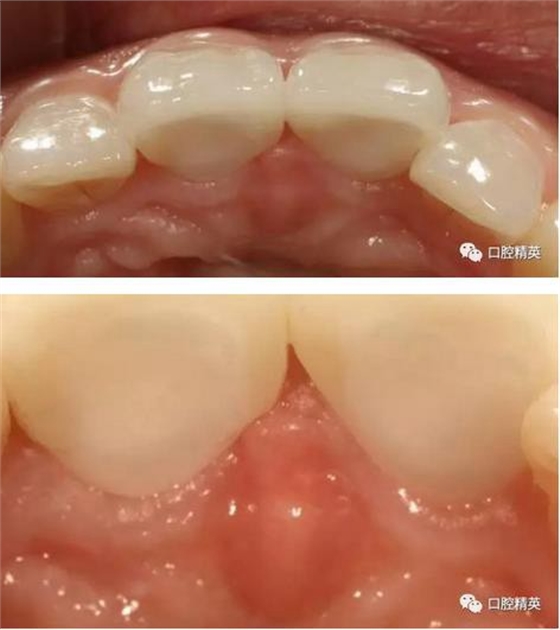

口內(nèi)正側(cè)位及切端特寫(xiě)

從側(cè)位照可看出遠(yuǎn)中切角略有回收

有一點(diǎn)不足之處在于齦緣的高低不完全一致,補(bǔ)救辦法同上——激光輕掃